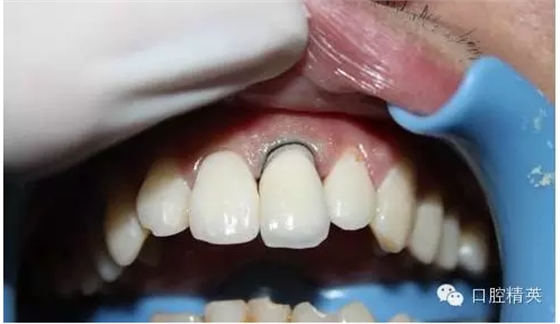

一年輕小伙,在打籃球中,被隊友打斷門牙,來本診所時已經(jīng)露髓,局麻拔髓后,行RCT。后因經(jīng)濟關系,擬鈷鉻樁加鈷鉻烤瓷冠修復,備牙后才留照片:

1:牙根,備牙后,

2:唇側(cè)觀,

3:鈷鉻金屬樁黏結(jié)后